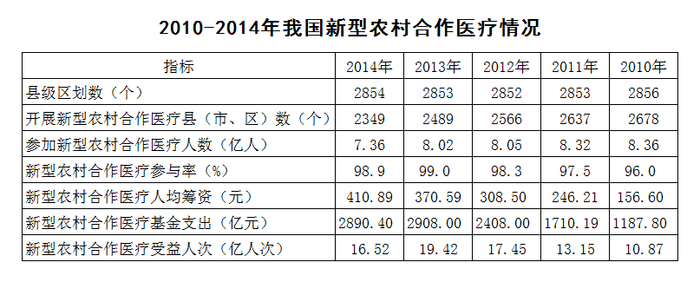

材料: 根据下列资料,回答91~95题: 2010—2014年我国新型农村合作医疗情况

第91题

2011—2014年,新型农村合作医疗基金支出同比增长幅度最高的是( )年。

- A. 2011

- B. 2012

- C. 2013

- D. 2014

答案: A

解析: 由“同比增长幅度最高”可知,本题为一般增长率的比较问题。定位表格可得2010-2014年新型农村合作医疗基金支出的具体值,则各项增速约为: A项:

;B项:

C项:

;D项同比下降,排除。 对比B、C两项,C项分子小、分母大,则分数较小,排除C项;对比A、B两项,分子增长约

,分母增长约

,分母增速更快,分数变小,则A项更大。 故正确答案为A。

第92题

2010—2014年,开展新型农村合作医疗的县(市、区)数量占县级区划数90%以上的年份有( )个。

- A. 1

- B. 2

- C. 3

- D. 4

答案: B

解析:

,即开展数量>县级区划数×0.9=县级区划数-县级区划数×0.1,即开展数量>县级区划数-县级区划数×0.1。定位表格可得2010-2014年我国新型农村合作医疗县级区划数与开展数,则 2014年:2349<2854-285; 2013年:2489<2853-285; 2012年:2566<2852-285; 2011年:2637>2853-285; 2010年:2678>2856-286; 满足条件的有2011与2010年两年。 故正确答案为B。

第93题

2011—2014年,新型农村合作医疗受益人次增长率最高的是( )年。

- A. 2011

- B. 2012

- C. 2013

- D. 2014

答案: B

解析: 由“增长率最高的是”可知,本题为一般增长率的比较问题。定位表格可得2010-2014年新型农村合作医疗受益人次的具体值,则各项增速约为: A项:

;B项:

;C项:

;D项同比下降,排除。直除可得,A项首位商2,B项首位商3,C项首位商1,则B项最大。 故正确答案为B。

第94题

2010—2014年,参加新型农村合作医疗人数最多的一年比人数最少的一年多了( )亿。

- A. 0.31

- B. 0.34

- C. 0.65

- D. 1

答案: D

解析: 定位表格可得,2010-2014年参加新型农村合作医疗人数最多的一年为2010年,8.36亿人;最少的一年为2014年,7.36亿人。故二者之差=8.36-7.36=1亿人。 故正确答案为D。

第95题

下列说法有误的是( )。

- A. 新型农村合作医疗基金支出逐年增加

- B. 参加新型农村合作医疗人数最少的一年也是人均筹资最多的一年

- C. 新型农村合作医疗参与率最高的是2013年

- D. 参加新型农村合作医疗人数最多的是2010年

答案: A

解析: 根据表格材料逐项分析,找出说法错误的一项。 A项:新型农村合作医疗基金支出在2014年出现下降,说法错误; B项:根据表格可知,人数最少的与人均筹资最多的均为2014年,说法正确; C项:新型农村合作医疗参与率最高的为2013年,说法正确; D项:参加新型农村合作医疗人数最多的是2010年,说法正确。 本题为选非题,故正确答案为A。